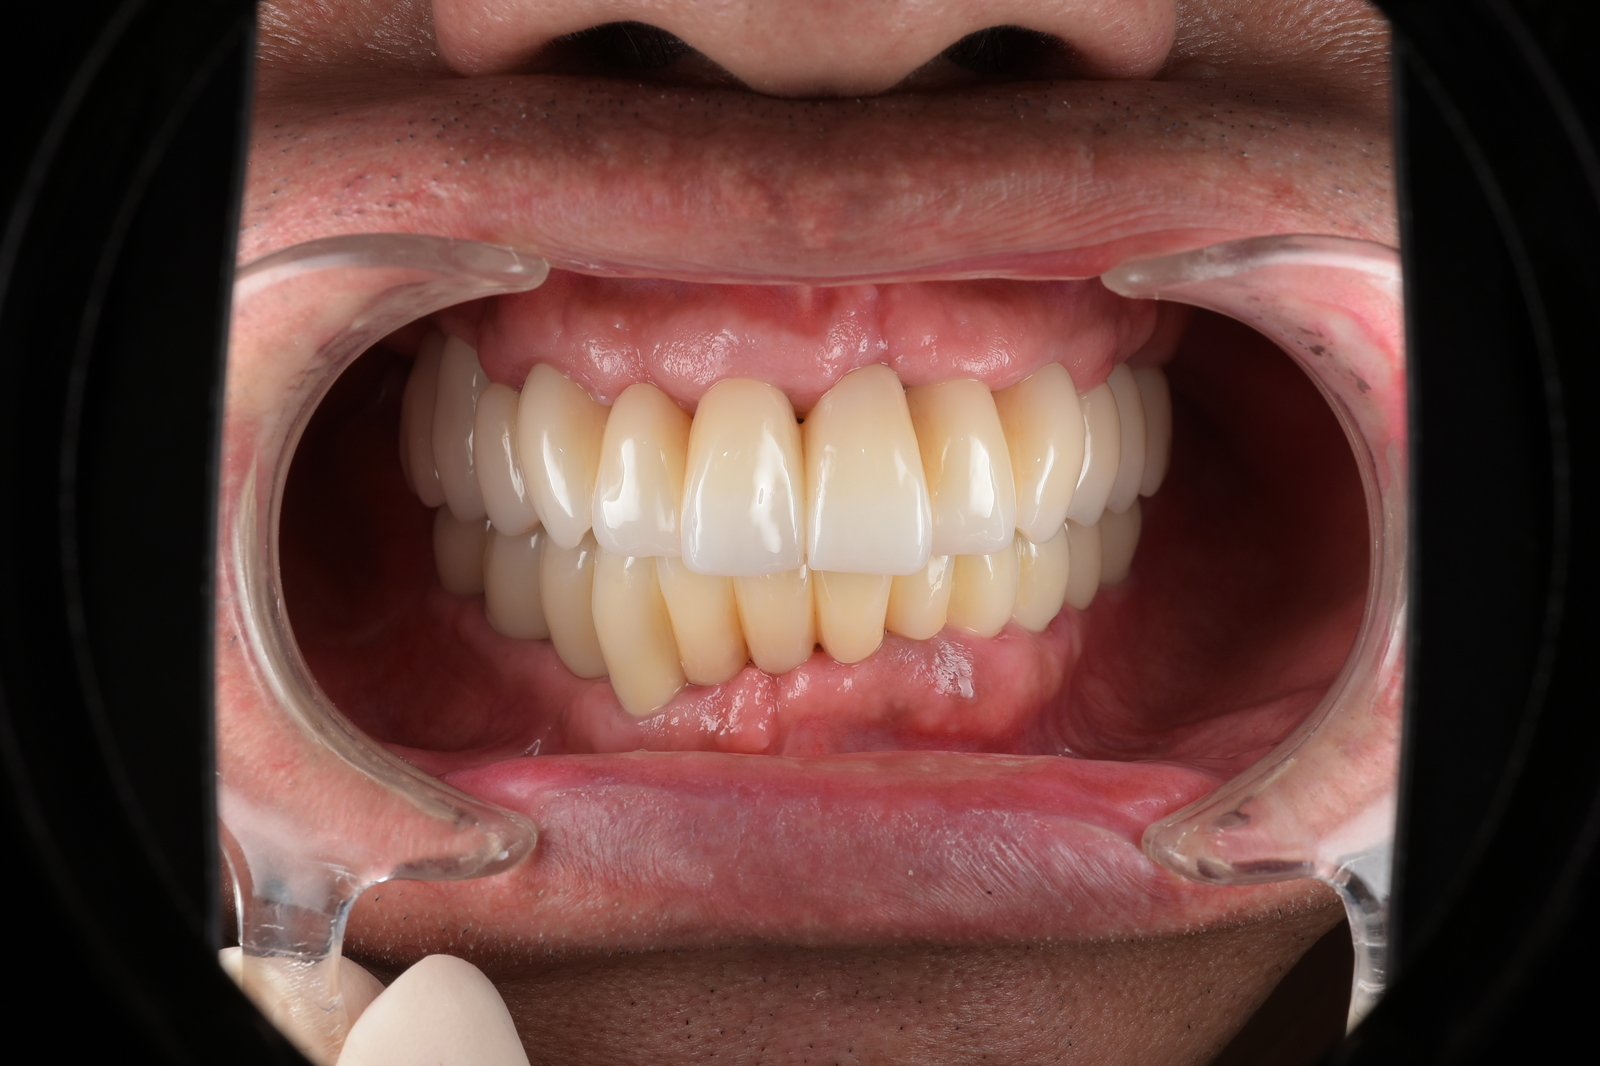

このページをご覧になっている方は、おそらく歯周病に関するお悩みの解決方法をお探しなのだと思います。

きっと、こうしている今も、歯周病が進行してグラグラしている歯があるのではないでしょうか。

皆さんもご存じかと思いますが、歯周病は、歯を支える骨をゆっくり溶かしていき、痛くもないのに歯が抜けていくという恐ろしい病気です。

しかし、心配は無用です。歯周病の原因とそのメカニズムは明らかになっており、早期に治療すれば歯を失わずに済みます。

今からでも遅くはありません。残された歯を守るために、一緒に治療をしていきましょう。